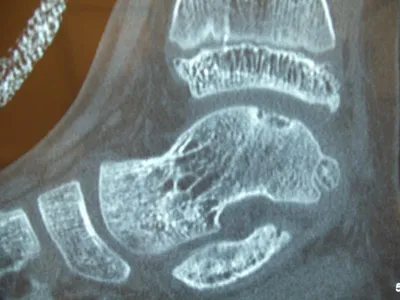

Series of Pics of Microfracture of large OCD of the Talar Dome

Pic of OCD after preparation and debridement .

Measuring the size and depth of the OCD.